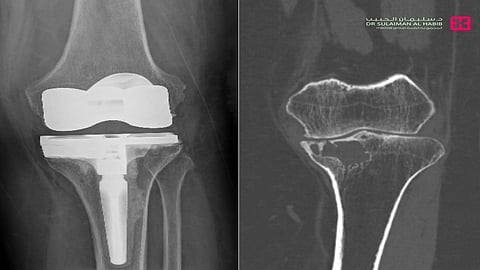

مشيراً إلى أن نتائج الفحوصات كشفت عن وجود ورم في عظمة الساق، مع خشونة شديدة في الركبة. وتم أخذ خزعة من الورم تحت اشراف طبيب الأشعة التداخلية، إذ تم تشخيص الورم بورم دموي حميد. مفيداُ بأنه تم تكوين فريق طبي من استشاري جراحة العظام والأورام والأشعة التداخلية والتخدير والعناية المركزة، وعقب دراستهم لكامل نتائج الفحوصات، تم اتخاذ القرار بالتدخل الجراحي العاجل،وذلك للحيلولة دون إصابة المراجعة بمزيد من الأعراض والمضاعفات الحادة، والمتمثلة في كبر حجم الورم وانتشاره في مواضع أخرى بالجسم.

موضحاً بأنه تم إخضاع المراجعة لجراحة دقيقة استغرقت ساعتين تحت التخدير العام، وتم فيها كحت الورم واستئصاله بالكامل، واستبدال مفصل الركبة في عملية معقدة ، وترميم الفجوة بواسطة دعامات خاصة.